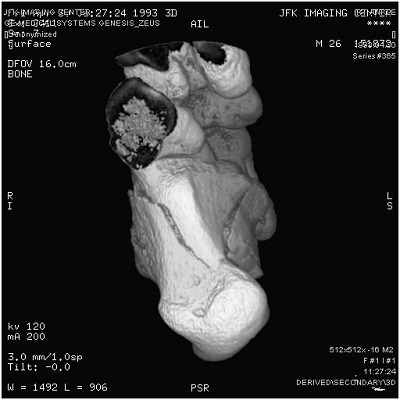

In most DICOM software, pressing the mouse button and dragging it left and right should allow you to control window width, and dragging it up or down should control the level. On other software, there might be two controls side by side which are marked W and L (always read your product documentation to be safe). See screen capture below from OsiriX software running on my machine at home showing the Window Width and Level functionality on a DICOM image.To sum up, a radiological workstation monitor would have permitted you to see all 65,536 shades of gray at once, but in a conventional monitor, or a cell phone for example, you will use W/L functions to navigate the entire range in small sized chunks at a time adjusting for the body part you want to zone in as well as adjusting for the viewing monitor’s capabilities and the user’s eye comfort at the same time. Most software will have presets for head, lung, etc to enable the radiologist to select these ranges quickly at the same time providing him/her with the ability to override these settings when necessary. Pretty cool, huh?